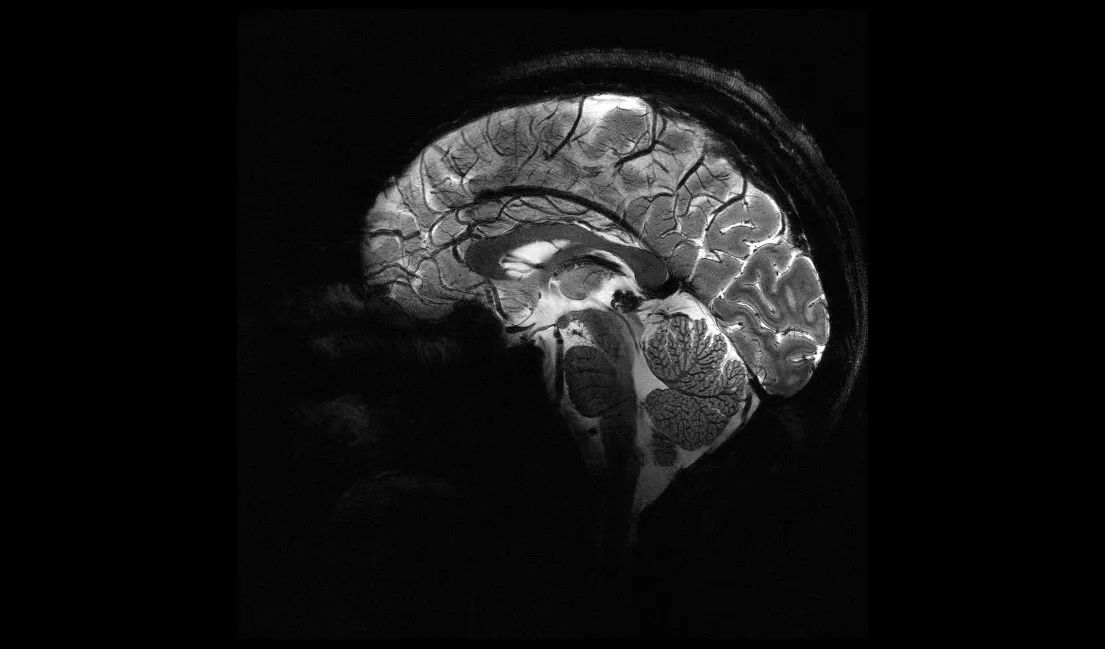

Le CEA a dévoilé des images du cerveau obtenues avec le scanner IRM Iseult, doté d'un champ magnétique de 11,7 teslas, le plus puissant au monde. Ces images offrent une résolution inégalée et permettent de découvrir de nouveaux détails sur l'anatomie, les connexions et l'activité du cerveau humain. Les applications médicales de cette avancée sont nombreuses, notamment dans le diagnostic et la prise en charge des maladies neurodégénératives comme Alzheimer et Parkinson. Le projet Iseult, qui a réuni près de 200 personnes, est le fruit de plus de 20 années de recherche et de développement au sein du CEA.